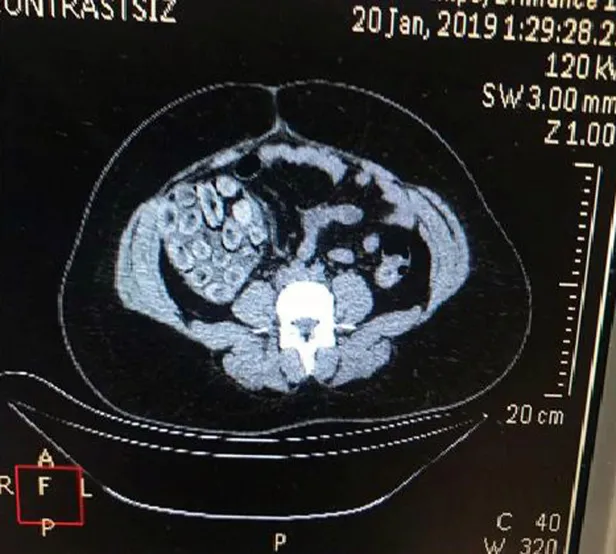

Ekipler yapılan aramada A.D.S.L.'nin uyuşturucu maddeyi kapsül halinde yutmuş olabileceğini değerlendirerek Haseki Eğitim ve Araştırma Hastanesine sevk etti. Hastanede sindirim sistemi röntgen filmi çekilerek kontrol edilen Brezilya uyruklu kadın A.D.S.L.'nin içinde kokain bulunan kapsül şekline soktuğu 115 prezervatifi yuttuğu belirlendi.